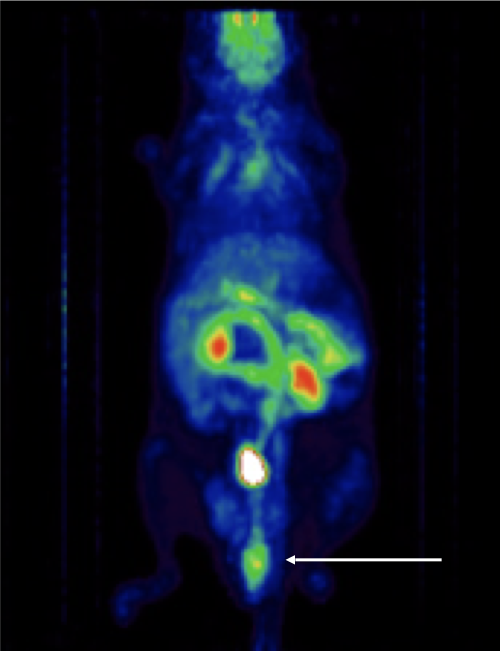

CASE 3: Mouse PET imaging of colorectal cancer

Research objective:PET imaging to detect colorectal cancer and possible metastasis in a specific knocked-out mouse model. Arrows show the lesion in mice of the KO group.

Animal model:Mouse, 20-25g

Acquisition protocol:10 min acquisition time, 1 bed position

Processing and reconstruction protocol:3D-OSEM, 0.42 x 0.42 x 0.855 voxel size

Biomarker or contrast agent:Mice were injected with ~10 MBq [18F]FDG in jugular vein (i.v.). Imaging at 1 h post injection.